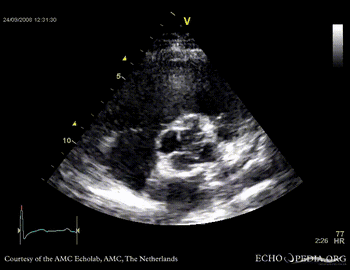

PLAX showing concentric left ventricular hypertrophy PLAX shows aortic regurgitation